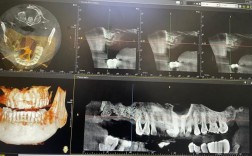

- 口腔CBCT(锥形束CT): 进行三维影像检查,精准评估牙槽骨的高度、宽度、密度,避开重要神经血管。